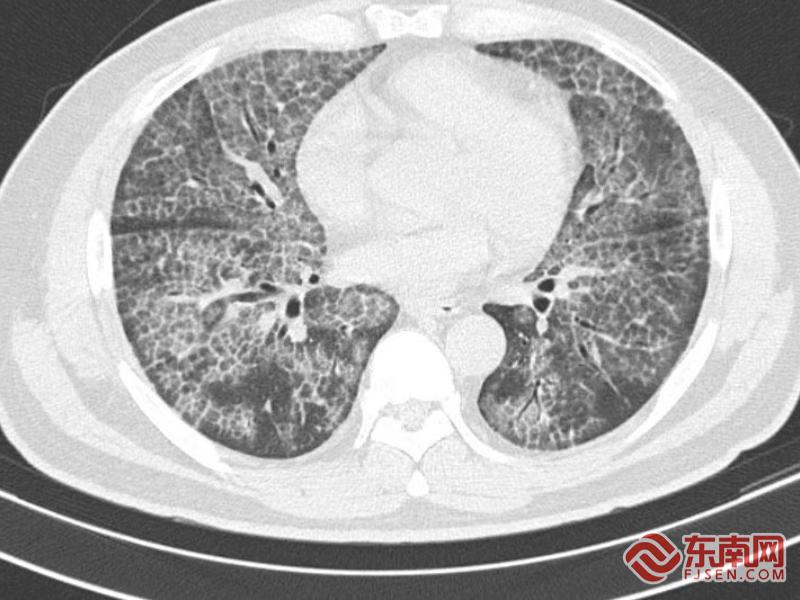

宁德市医院副院长、呼吸与危重症科主任医师薛青耐心问诊并完善肺部 CT 检查后,初步判断其为极为罕见的肺泡蛋白沉积症,他安抚患者,可为肺部 “洗个澡”,缓解病症。后续经气管镜肺活检等检查,林先生最终确诊该病。

影像图。宁德市医院供图

方桂桔表示,肺泡蛋白沉积症是以肺泡腔及细支气管内沉积大量非脂溶性磷脂蛋白样物质为主要特征的一种极其罕见肺部疾病,发病率仅为3.7/100万。主要可表现为咳嗽、呼吸困难及咳痰,也可表现为咯血、乏力、胸痛等不典型症状。目前全肺灌洗仍是主要的治疗方法,即在全身麻醉状态下行双腔支气管插管,一侧肺通气,一侧肺灌洗,反复予 37℃生理盐水灌洗,采用物理手段清除肺泡表面活性物质,以缓解临床症状。在此,特别提醒:如出现长时间不明原因咳嗽、活动后气喘等症状,应及时就医,避免延误诊治。